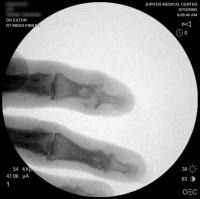

Distal interphalangeal erosive osteoarthritis severe enough that the diagnosis of giant cell or other tumor was suspected. Fortunately, no tumor was encountered at surgery.

Xrays one year out.

Progressive PIP changes remain a problem.